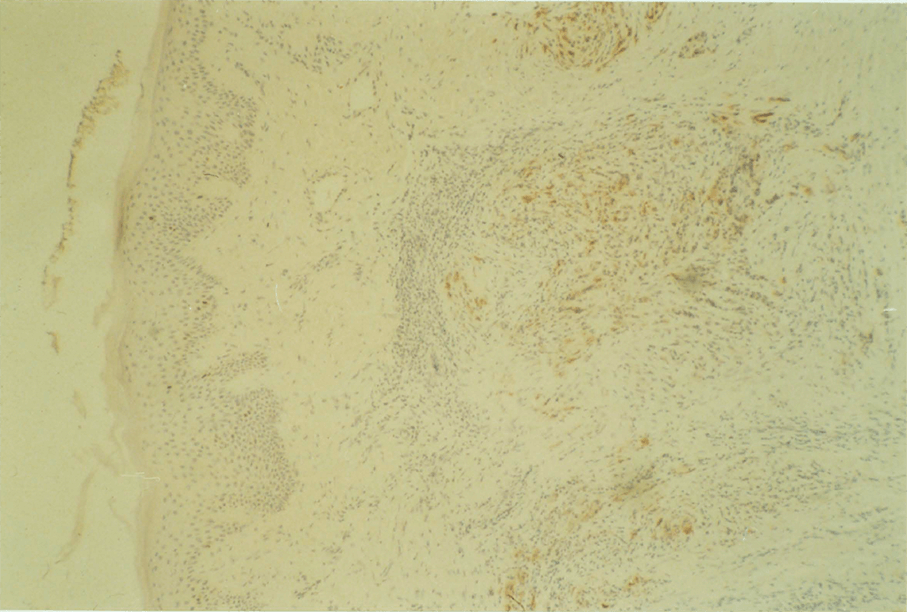

8:1. The staining procedure for the p62c-myc protein.

8:3. p62c-myc levels in colorectal tissues and tumours

8:4. Results: p62c-myc levels in colorectal tissues and tumours compared with BRdU labelling.

8:5. Results: p62c-myc levels in colorectal tissues and tumours compared with the Tpot.

8:6. Photomicrograph of polyposis coli mucosa stained for p62c-myc protein.